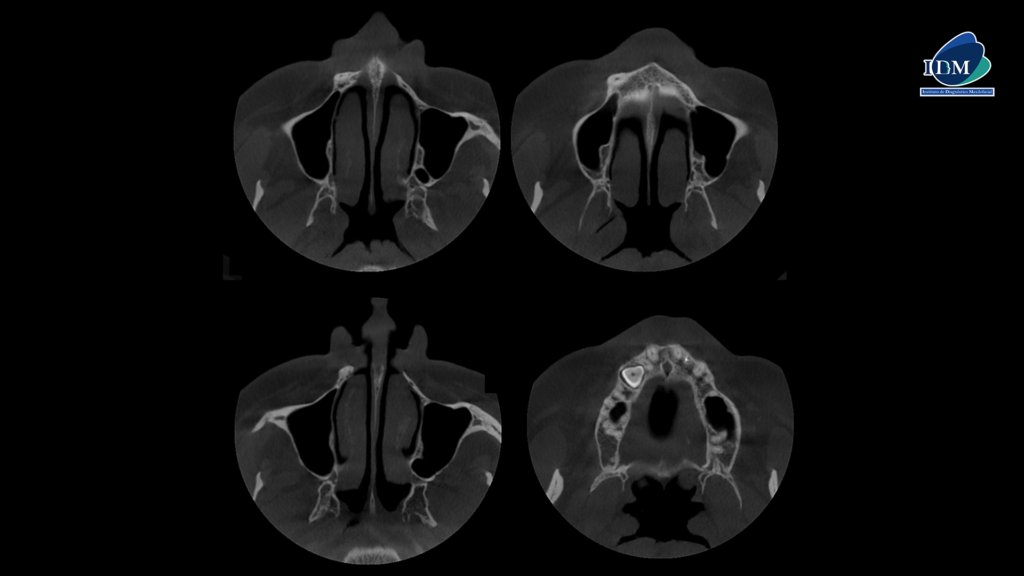

Así mismo en la tomografía volumétrica de haz se evidencia que dicha pieza esta distoangulada con el segmento coronario orientado hacia palatino y el segmento radicular orientado hacia vestibular, conservando el espacio del ligamento periodontal en toda su trayectoria.

CORTES AXIALES

- Pieza 1.3 impactada en posición ectópica.